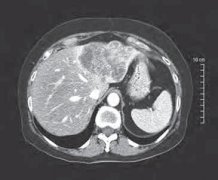

胰腺炎影像:谁需要治疗?谁又需要介入?谁要该做什么样的介入?

点击:99

由于多功能脏器衰竭,胰腺炎死亡的一半发生在这一期。第二期,发生在第一期后的1-2星期,其特征是代偿性抗炎性反应综合征(compensatory anti-inflammatory response syndrome,CARS,也有称 counteractive anti- inflammatory response syndrome*。CARS期的...